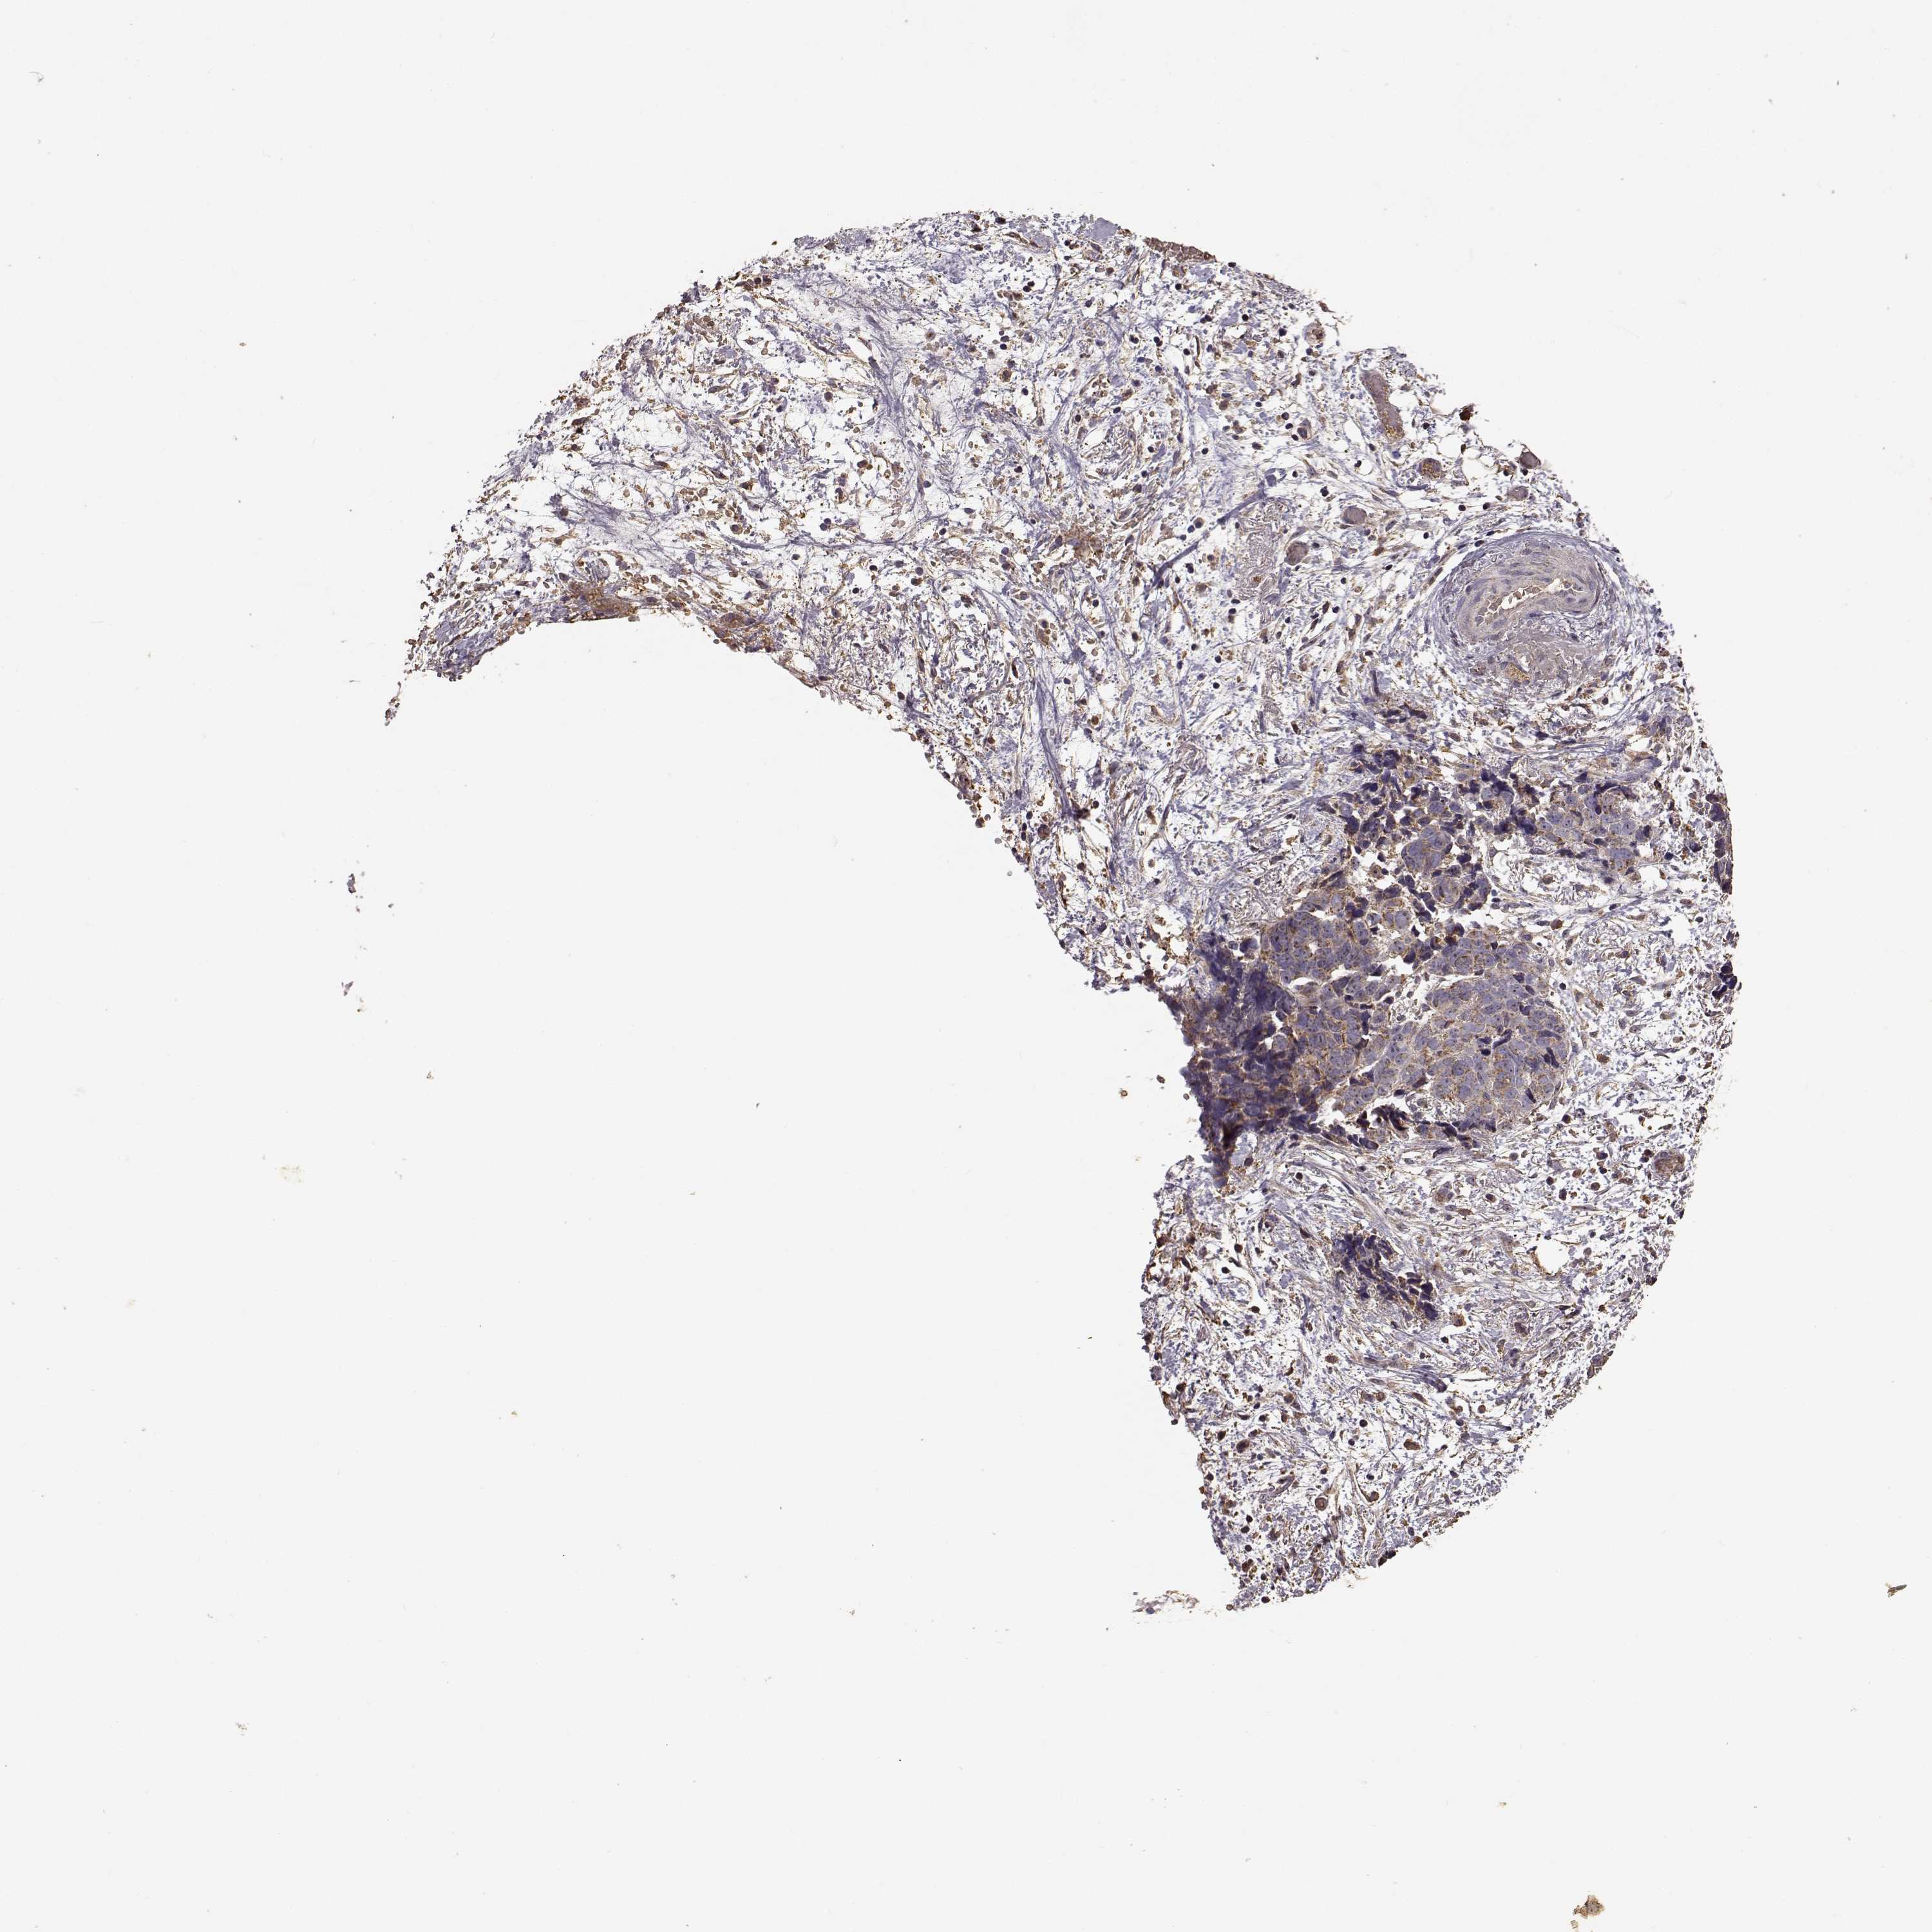

OVARIAN CANCER - Protein expressioni

A mouse-over function shows sample information and annotation data. Click on an image to view it in a full screen mode. Samples can be filtered based on level of antibody staining by selecting one or several of the following categories: high, medium, low and not detected. The assay and annotation is described here.

Note that samples used for immunohistochemistry by the Human Protein Atlas do not correspond to samples in the TCGA dataset.

Antibody stainingi

Antibody staining in the annotated cell types in the current human tissue is reported as not detected, low, medium, or high, based on conventional immunohistochemistry profiling in selected tissues. This score is based on the combination of the staining intensity and fraction of stained cells.

Each image is clickable and will lead to virtual microscopy that enables deeper exploration of all samples and also displays staining intensity scores, fraction scores and subcellular localization as well as patient and tissue information for each sample.

Antibody HPA020733

Staining

High

Medium

Low

Not detected

Intensity

Strong

Moderate

Weak

Negative

Quantity

>75%

75%-25%

<25%

None

Location

Nuclear

Cytoplasmic/membranous

Cytoplasmic/membranous,nuclear

Cystadenocarcinoma, serous, NOS

Cystadenocarcinoma, mucinous, NOS

Carcinoma, endometroid